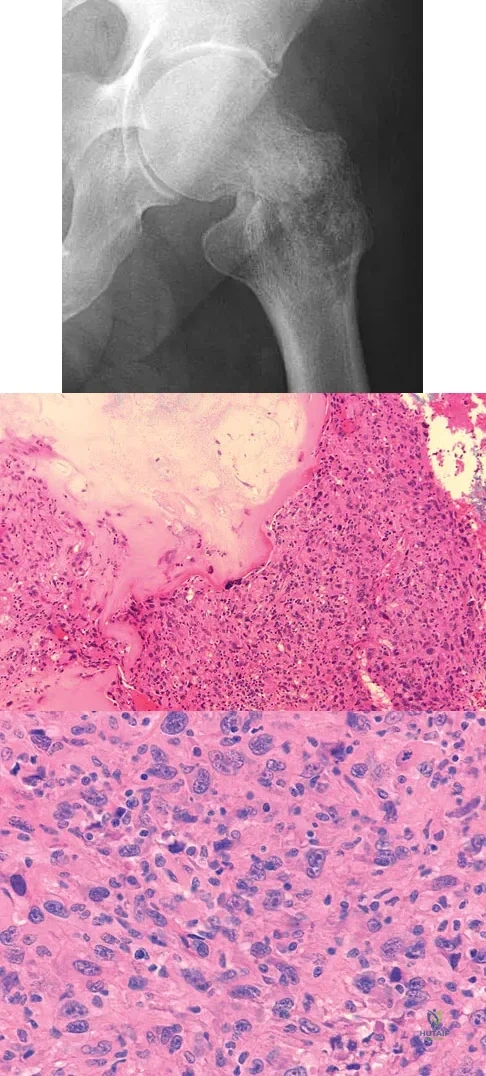

A 73-year-old man stepped off a street curb and felt a crack in his left hip. He is now unable to bear weight. A radiograph is shown in Figure 54a. Biopsy specimens are shown in Figures 54b and 54c. What is the most likely diagnosis?

Explanation